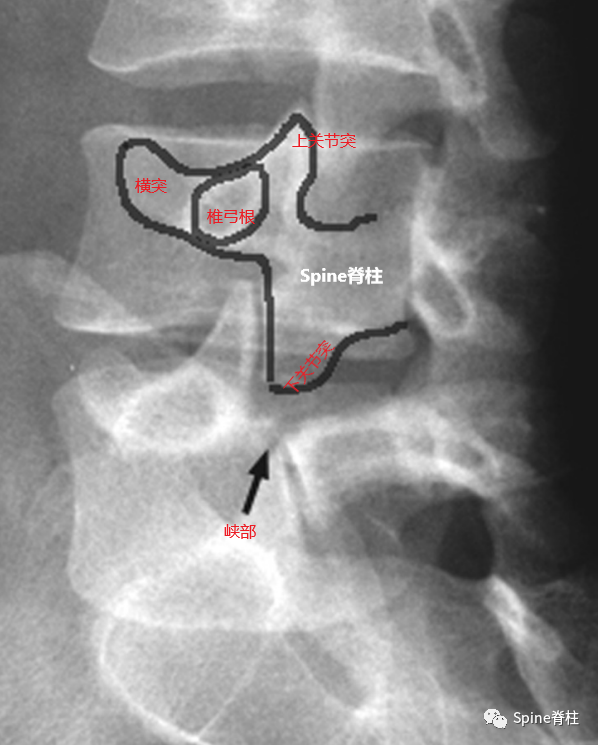

腰椎峡部在腰椎斜位片上常比喻为苏格兰狗(Scotty dog)的脖子

椎弓崩裂征象:X线腰椎45°斜位摄片示上关节突轮廓似"狗耳",横突似“狗头/嘴”,椎弓根似“狗眼”,下关节突似“狗前肢”,关节突肩部或称峡部似“狗颈部”。椎弓峡部崩裂时,“狗颈部”可见裂隙。

腰椎斜位片上的苏格兰狗和断裂的脖子(峡部裂)

再回顾下腰椎斜位视角的模式图,圆圈处为峡部